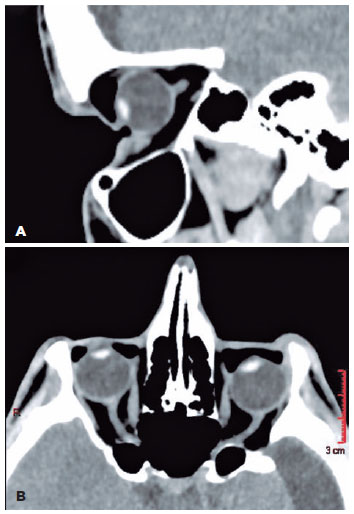

A 27-year-old Caucasian man with a history of idiopathic congenital hydrocephalus who underwent VPS was referred to the Porto Alegre Eye Bank Hospital with complaints of “sinking of the eyeballs” and ocular irritation in both eyes and a progressive decrease in vision in the left eye (OS). Examination revealed severe bilateral asymmetrical enophthalmos, flat anterior chamber, upper-half erosive keratopathy, and 3-mm superonasal corneal perforation with iris prolapse in the OS. No corneal infiltration or infectious keratitis was observed. Initial examination revealed 20/25 best corrected visual acuity in the right eye (OD) and hand movement in the OS. Ocular motility presented a marked reduction in infraduction OS (Hertel exophthalmometer value of 6 mm OD and 4 mm OS) and eyelid imbrication associated with lower eyelid entropion (Figure 1). The lacrimal drainage system was normal. Severe bilateral enophthalmos due to upward bowing of the orbital roof with significant widespread air under the eyelids, short and straight optic nerves, and enlarged maxillary, ethmoid, and sphenoid sinuses were evident on orbital computed tomography (CT) scan (Figure 2). Under general anesthesia, the patient underwent therapeutic full-thickness 8.25-mm keratoplasty the next morning. The surgical procedure was technically difficult because of the remarkable enophthalmos and restriction of infraduction that created poor exposure. Host graft microbiological cultures were negative for fungal and bacterial infections. Over the next 3 months, penetrating keratoplasty maintained the ocular integrity and improved vision of hand movement to 20/30. The following month, the patient was admitted for shunt revision of intracranial hypotension and for left orbital roof reconstruction with a costochondral graft under general anesthesia through orotracheal intubation. The rib graft was harvested from the right seventh and eighth costal cartilage and contoured in the cavities to correct the shape of the left orbit. The segments were stabilized and accommodated superiorly, inferiorly, nasally, and temporally. An excellent reduction of enophthalmos to a Hertel exophthalmometer value of 10 mm was noted, which restored the contact between the palpebral conjunctiva and left globe, reducing the signs of exposure keratopathy (Figure 3).

02-fig02.jpg)

Figure 2. (A) Sagittal and (B) axial CT scans show localization of various abnormal air spaces and deepened upper and lower eyelid sulci pulled into the expanded orbits. The images are also oriented to show the entire orbital and part of the intracanalicular segment of the optic nerves to show the lack of redundant optic nerve length.